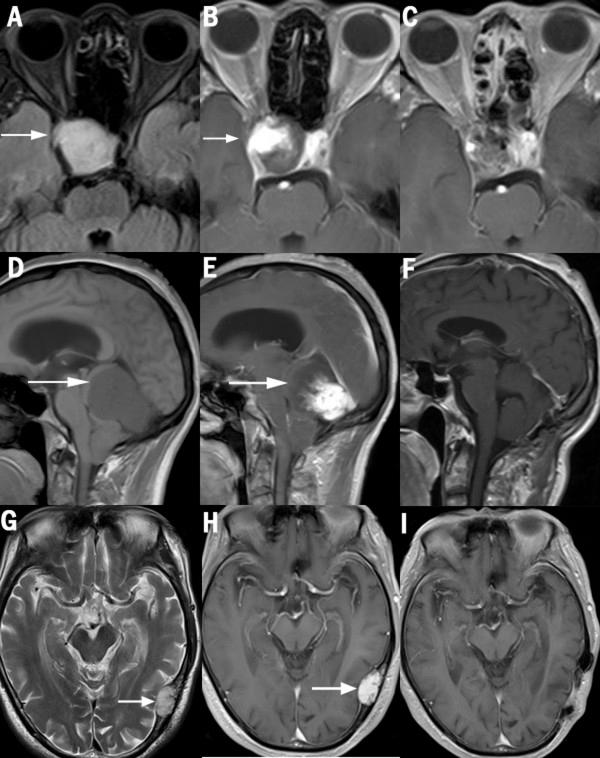

Three cases of intracranial angioleiomyoma (ALM) in our neurosurgery center are reported in detail. ALM is a benign soft tissue tumor comprised of mature smooth muscle cells and a prominent vascular component, which is extremely rare as a primary intracranial lesion. Altogether, only 12 cases were recorded in the literature to date, to the best of our knowledge. Case 1 is the second report of intra-sella ALM, a 51-year-old woman presented with visual deterioration for 2 months. An MRI showed an intra-sella 3-cm tumor, partially flame-like, enhanced with gadolinium. Using microscopic endonasal transsphenoidal approach, the tumor was completely resected with great difficulty. At 11 days post-surgery, she died of a sudden catastrophic nasal hemorrhage. An angiography revealed a pseudo-aneurysm of ICA (internal carotid artery). Case 2 is a 49-year-old man who presented with weakness of the lower limbs for 1 year. A large subtentorial mass was found affixed to the torcular and straight sinus, which was partially flame-like, dramatically enhanced as in case 1. Case 3 is that of a 77-year-old man. An ALM mass was revealed in the diploe of left temporal bone, and had eroded the inner table. Immunohistochemical workup confirmed the diagnosis of angioleiomyoma in all 3 cases. The radiology, operation, and complication of surgery in each case were discussed. In conclusion, intracranial ALMs are extremely rare, usually located ex-neuro axis (such as in our cases), in the sella, in posterior fossa, or in the skull. Magnetic resonance imaging (MRI) revealed a special feature of flame-like partial enhancement that may be helpful to distinguish ALM from pituitary tumors or meningiomas, and should result in the consideration of this rare tumor entity early on in the diagnostic process. A definitive diagnosis depends on histological analyses. The resection of ALM in certain locations is difficult and risky because of the rich blood supply.